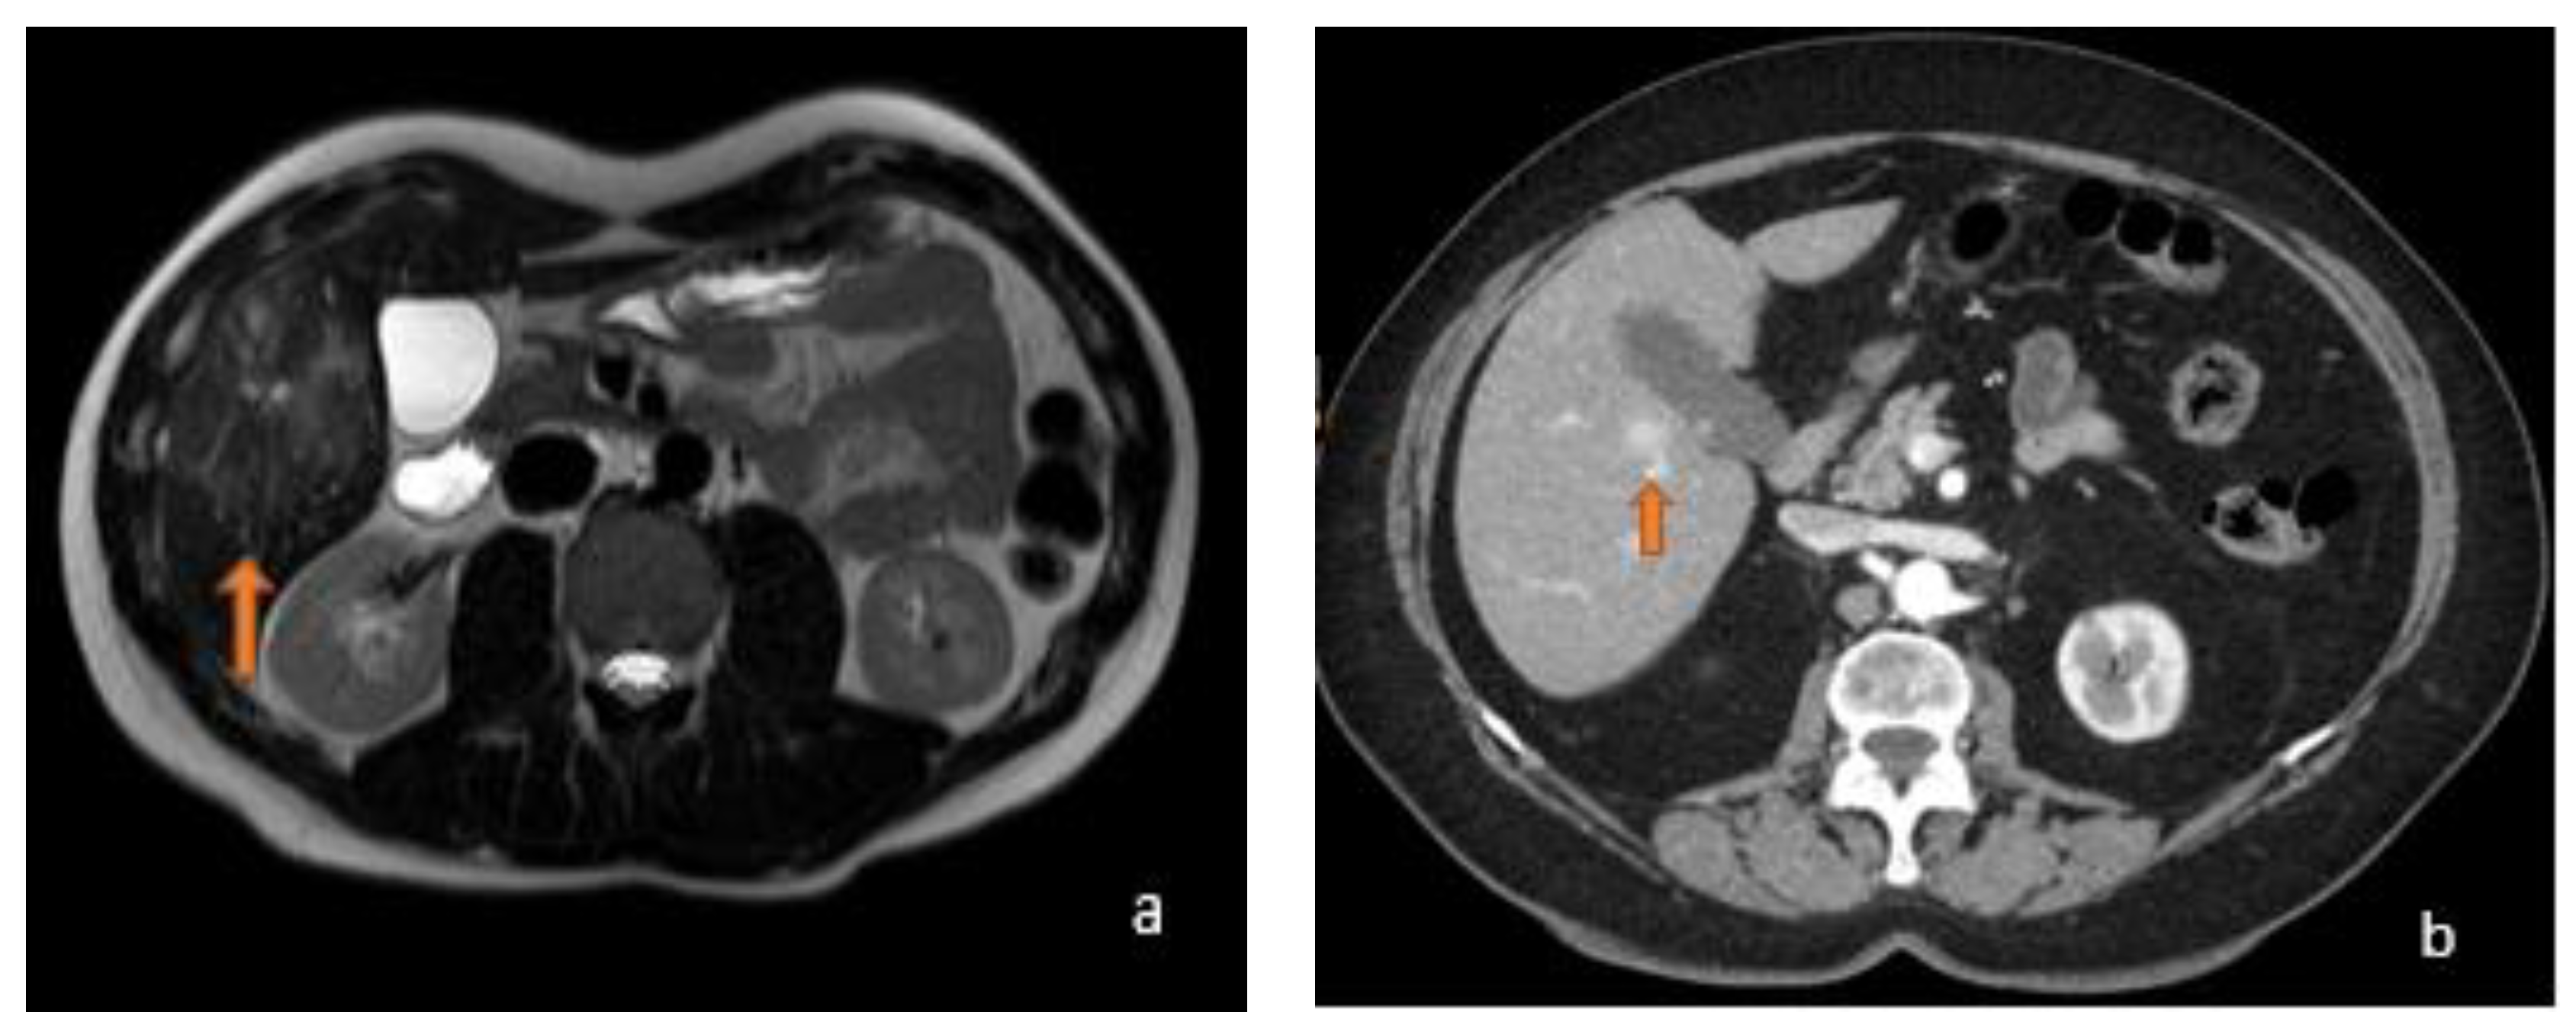

3.1. FLL Feature Characteristic

5.1. FLL Feature Characteristic